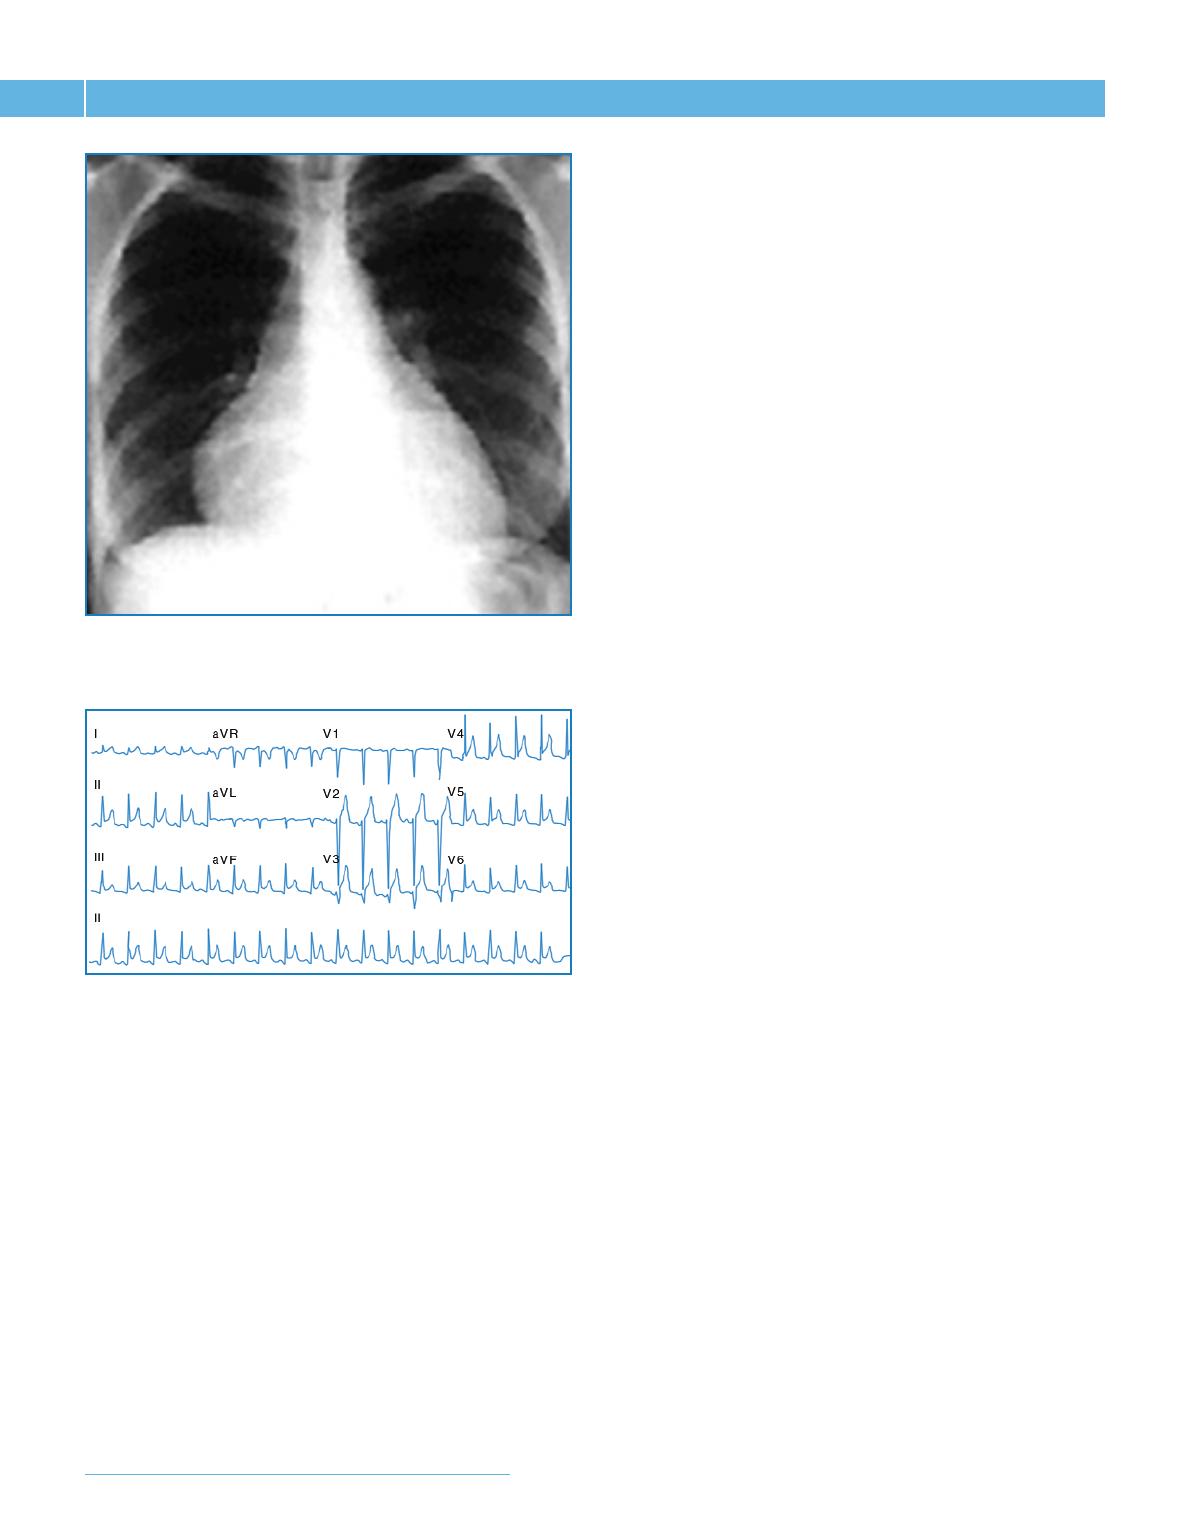

Le diagnostic de péricardite dans sa forme aiguë repose sur une triade

comprenant la douleur péricardique, la fièvre et le frottement péricar-

dique. Des anomalies de la radiographie thoracique avec augmentation

de taille de l’ombre cardiaque (fig. 1) et/ou épanchement pleural sont fré-

quemment observées. L’électrocardiogramme montre des anomalies diffuses,

non systématisées (fig. 2), d’évolution variable dans le temps. La forme “idio-

Fig. 1 : Radiographie thoracique montrant au cours d’une péricardite aiguë

une majoration de l’ombre cardiaque, en rapport avec l’épanchement.

Fig. 2 : Electrocardiogramme 12 dérivations d’un patient ayant une

péricardite aiguë montrant une élévation diffuse du segment ST.